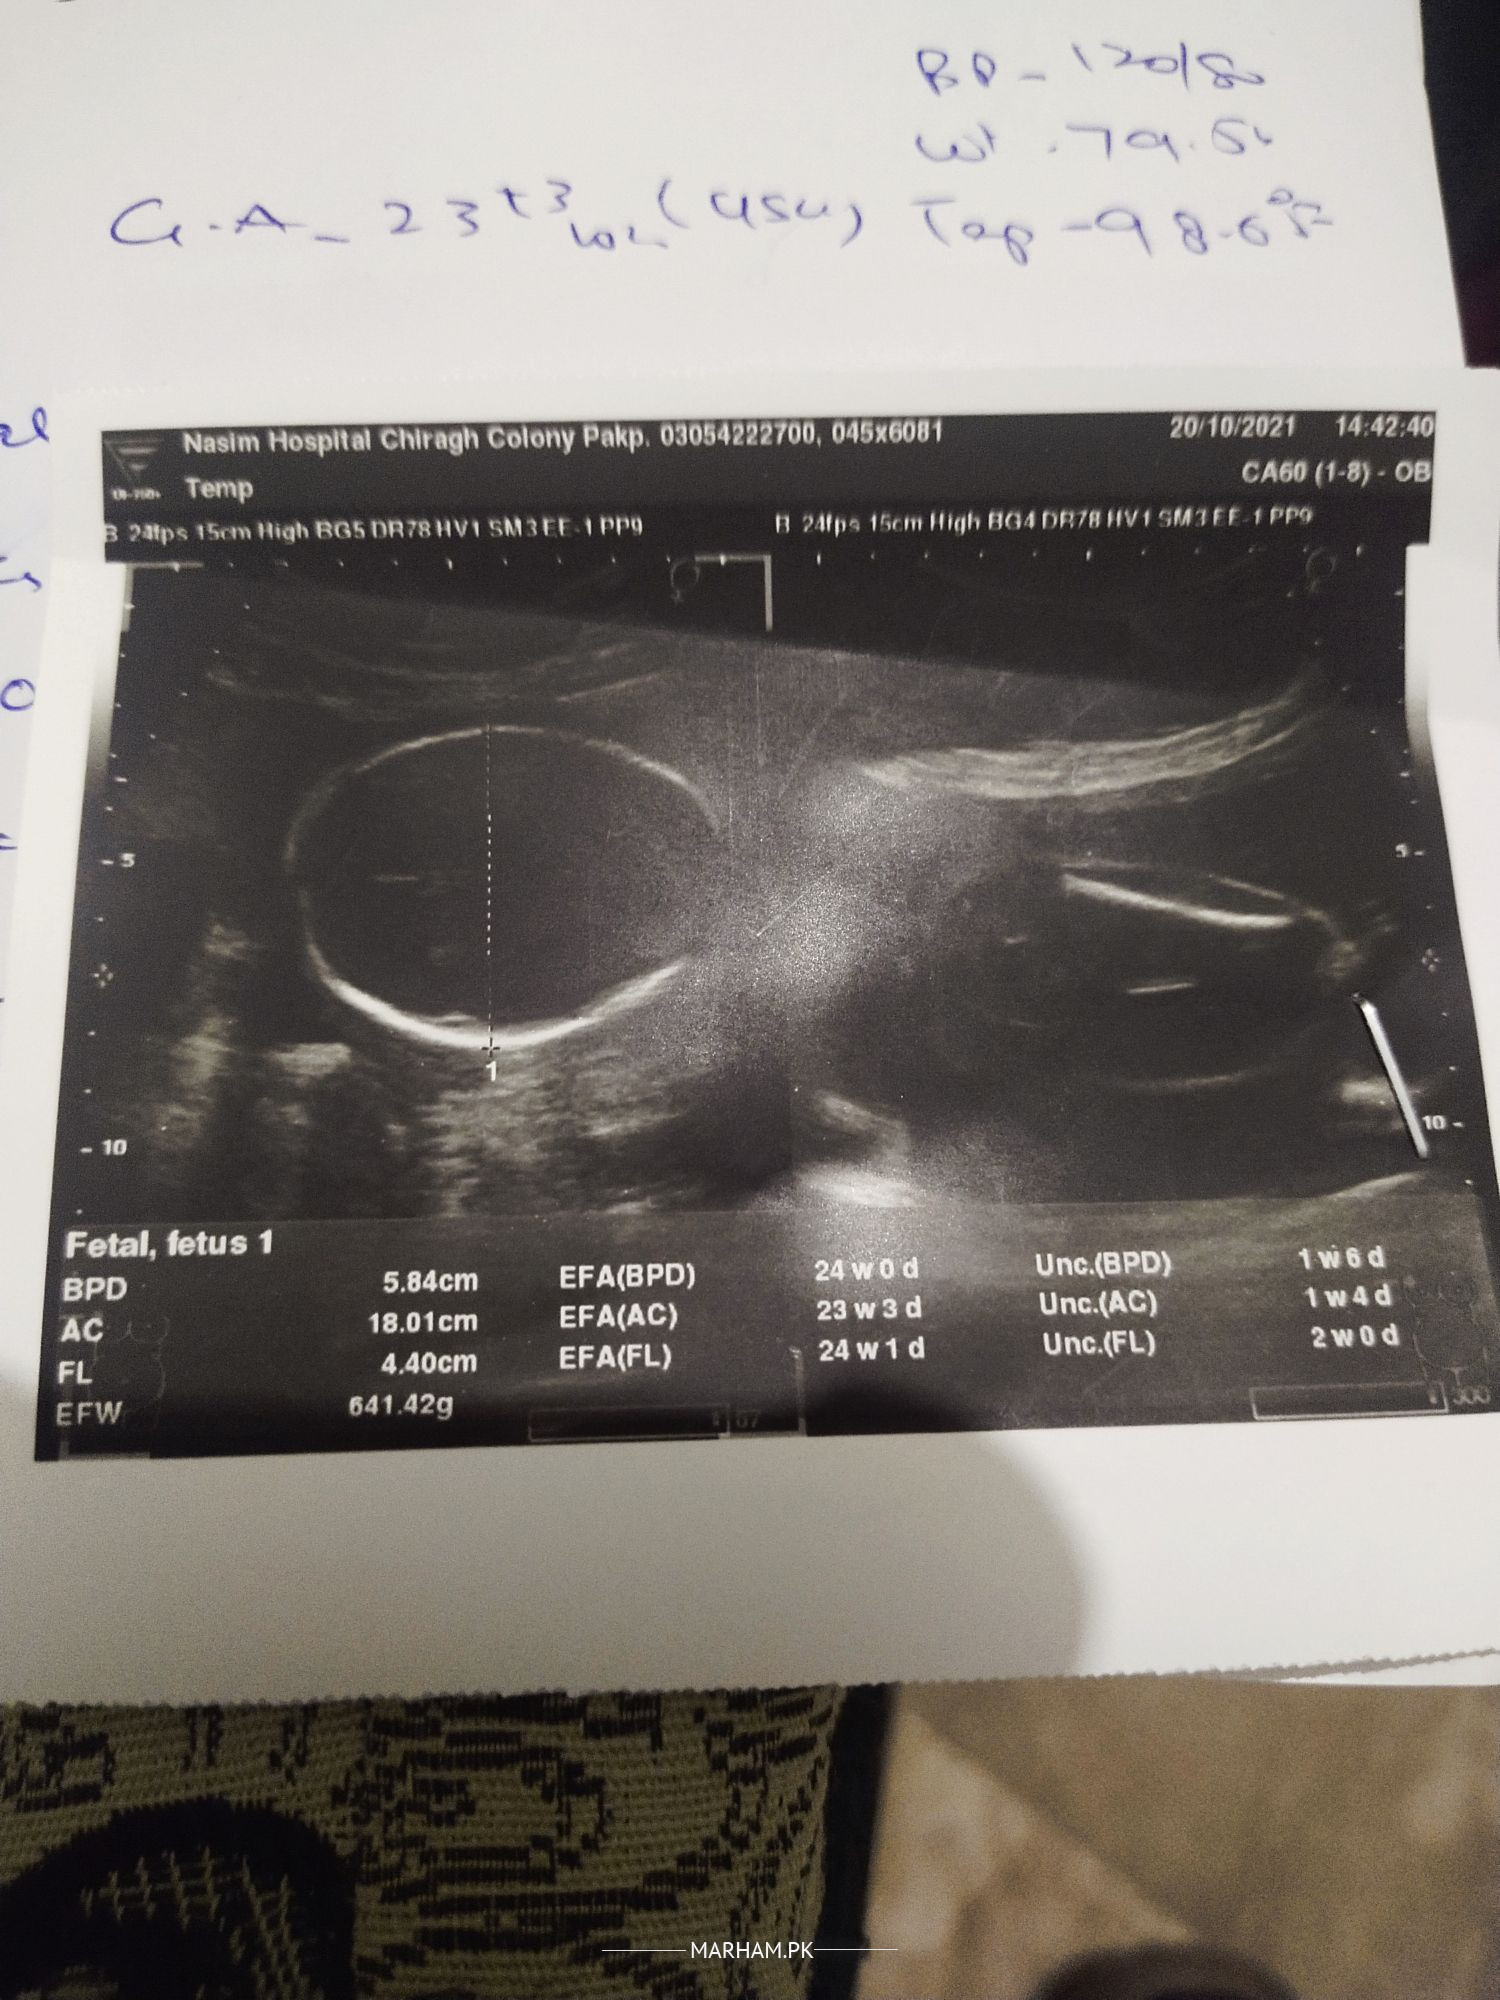

Aoa I have a question Kindly Ap bta skti ess ultrasound sy k Baby boy hy ya girl hy keonky mri doctor sahiba Ny 2 bar pocha unsy woh kehti han k Jo bhi hy Allah ko malom but mjhy malom krna please inform me

You have to do repeat ultrasound for gender of baby

It would be better to ask the person who actually performed the scan ? The images you posted are not meant for gender identification ?